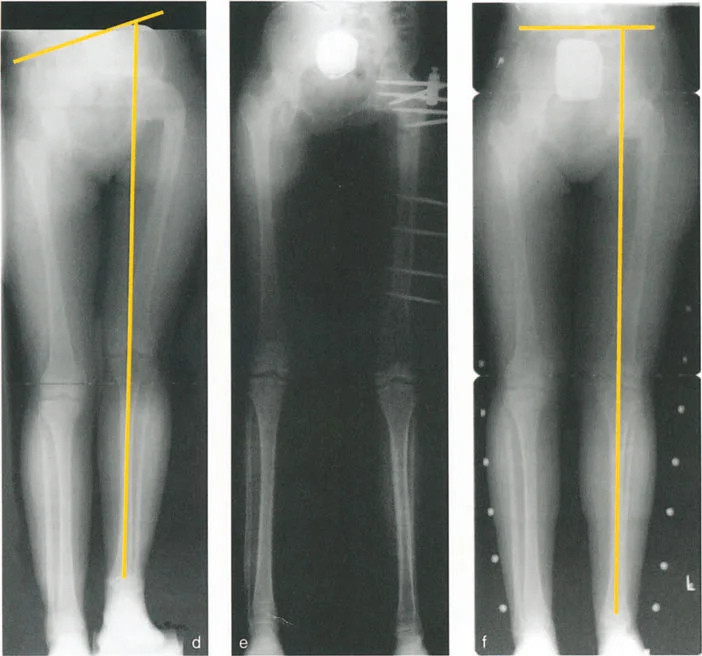

التقييم الإشعاعي وتجنب خطأ الالتواء

تُعد الأشعة السينية (X-rays) هي الخطوة الأولى والأساسية في التقييم الإشعاعي. ومع ذلك، فإن مفصل الورك معقد، وقد تتطلب بعض التشوهات صورًا إشعاعية خاصة.

- الأشعة السينية التقليدية: تُظهر صور الأشعة السينية الأمامية الخلفية (AP) والجانبية (Lateral) للورك العظام الرئيسية وتساعد في الكشف عن التشوهات الواضحة.

- صور الأشعة الجانبية عبر الطاولة (Cross-table lateral view): تُعد هذه الصورة حاسمة لتقييم الزاوية الأمامية لعنق الفخذ (ANSA) وتحديد التشوهات في المستوى السهمي. يُشدد الأستاذ الدكتور محمد هطيف على ضرورة الحصول على هذه الصورة بشكل صحيح، بحيث تكون موجهة بالنسبة لـ "المنظر الأمامي الحقيقي للورك" وليس الركبة، لتجنب ما يُسمى "فخ الالتواء".

فخ الالتواء (The Torsional Trap): إذا كان هناك تشوه التوائي شديد في عظم الفخذ (مثل زيادة في الميل الأمامي لعنق الفخذ)، فإن المنظر الأمامي الحقيقي للركبة (الرضفة متجهة للأمام) سيكون مختلفًا تمامًا عن المنظر الأمامي الحقيقي للورك. إذا قام فني الأشعة بالحصول على الصورة الجانبية عبر الطاولة بشكل عمودي على المنظر الأمامي الحقيقي للركبة بدلاً من الورك، فقد تظهر الزاوية الأمامية لعنق الفخذ وكأنها مُنثنية بشكل ملحوظ في الفيلم. هذا يخلق تشوه انثناء ثابت ظاهري للورك، وهو في الواقع خطأ ناتج عن الدوران وليس تشوهًا سهميًا حقيقيًا.

القاعدة التشخيصية: لا يتم تأكيد وجود تشوه انثناء ثابت حقيقي ناتج عن انحناء هيكلي في عنق الفخذ إلا إذا ظهرت الزاوية الأمامية لعنق الفخذ مُنثنية بشكل ملحوظ، وتطابقت الصورة الجانبية عبر الطاولة للورك تمامًا مع المنظر الجانبي الحقيقي للركبة.